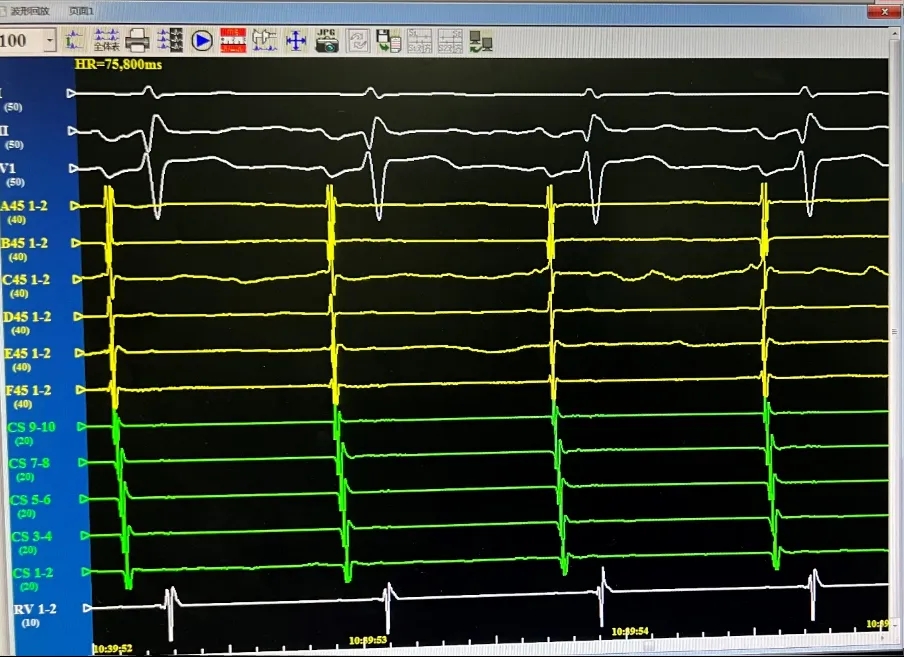

术中均直接采用CardiPulse®脉冲电场消融自身标测电极进行了电位标测,消融即刻及消融结束后四根肺静脉电位消失并双向传导阻滞,结果满意。

LSPV,消融前后电位。消融后电位即刻消失。

LIPV,消融前后电位。消融后电位即刻消失。

RSPV,消融前后电位。消融后电位即刻消失。

RIPV,消融前后电位。消融后电位即刻消失。

消融后电位验证

消融完成后,分别进行四支肺静脉电位验证。电位无恢复,证明传入阻滞。起搏电极,无法带起心房证明传出阻滞。